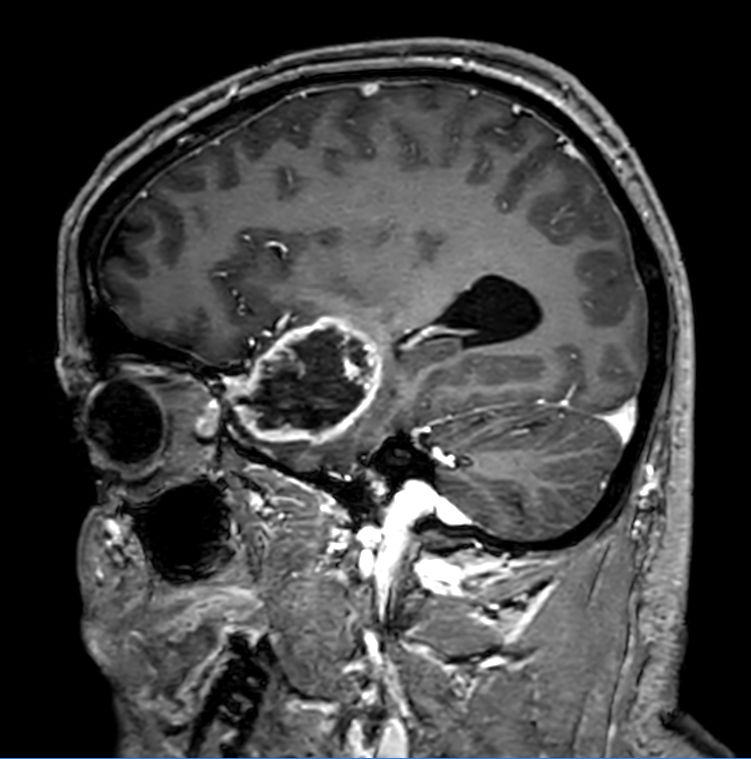

Sagittal 3D T1w TFEPost-Gado